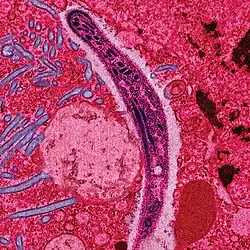

False-colored electron micrograph showing a malaria sporozoite migrating through the mosquito midgut epithelial cell